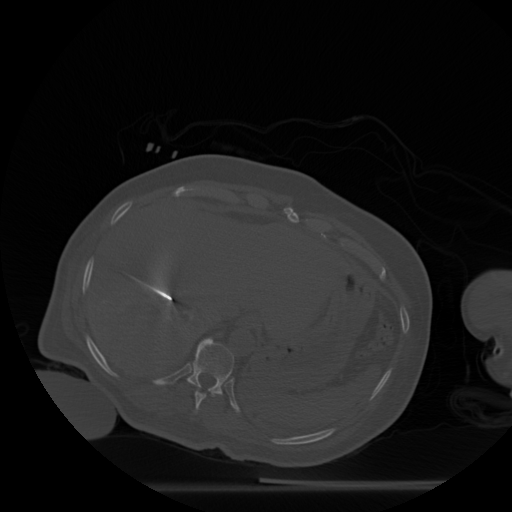

Figure 3: Radio-frequency ablation dataset. (a) through (g): one of the slices (512 x 512) from each of the 8 scan volumes of a longitudinal study dataset of the liver. Note that in volumes (a) through (g), the needle (shown in red in (f)) approaches the target tumor. (h) the organ after the ablation: this slice is displayed on a separate intensity scale to enable proper viewing of the region marked in green that shows the after-effects of ablating the tumor.

The dataset from this longitudinal medical study consists of 8 scans taken during the ablation procedure. We demonstrate our method for 2D reconstruction by choosing a single slice from each of the 8 volumes as our dataset. Note that all these 8 slices are located at the same index 222The notion of same index (slice number corresponding to the same depth) makes sense in the context, because in such problems, the different scans are aligned with each other. within each of the respective volumes. Fig. 3 shows the chosen set of 2D slices (each of size 512×512512512512\times 512) from the different volumes. Observe that the needle is seen in all of the first 7 slices and the effect of ablation is seen in the 8th slice.

Tracking the needle: We first choose slices 1-6 as our templates, and reconstruct slice 7 with the specific goal of tracking the needle and simultaneously reduce artefacts. Fig. 4 shows the reconstruction of slice 7 from its measurements from only 90 views. The reconstructions are quantitatively compared using SSIM.

Observing details of the ablation: Next, we choose slices 1-7 as our templates and reconstruct slice 8 from 120 views i.e., a somewhat higher number of views this time. Fig. 5 shows the reconstructions of slice 8 by different methods. We see that the weighted prior reconstruction brings in the advantage of the prior without it adversely affecting the new regions.